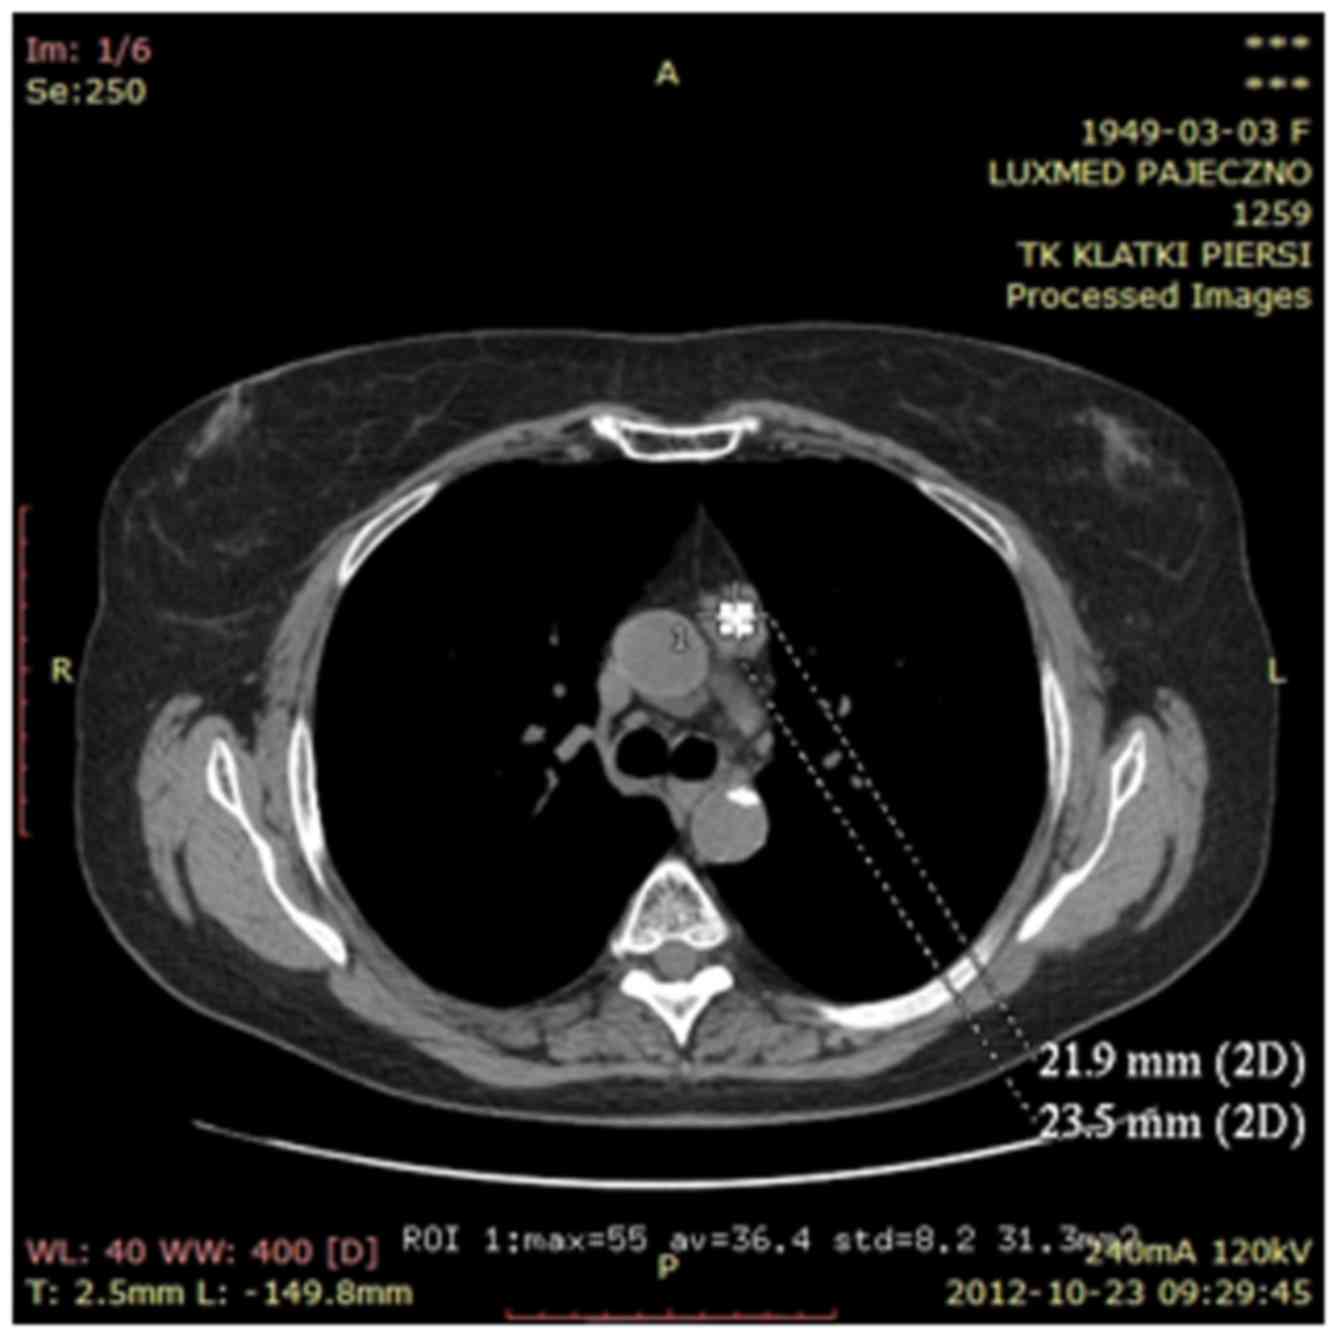

In April 2012, a computed tomography-positron emission tomography scan was performed in order to exclude neoplastic changes in the lymphnodes and metastatic disease. Gamma Knife was then used to treat mediastinal lymphnodes suspected for neoplastic infiltration. Oncological treatment was completed in May 2012 (Figs. 3 and 4). The patient was advised to visit the oncological centre in case of tumour progression detected on annual follow-up examinations.

Figure 4.

Computed tomography imaging showing regression of metastatic lesions in the liver after chemotherapy treatment.